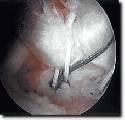

Pic Title: ouch

Pic Description: the results of a serious highside at cadwell